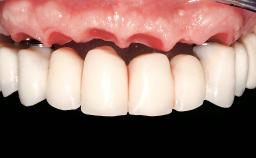

Immediate Loading of Six Implants in the Mandible and Six Implants in the Maxilla and Final Restoration with Full-Arch CAD/CAM Metal Framework FDPs Involving Digital Planning and Guided Surgery